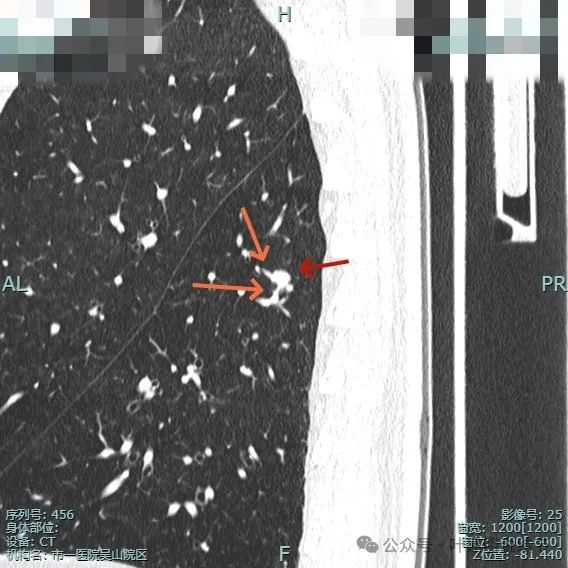

像个腰子的形态,靠下侧深凹进去,说明有收缩力吗?还是月牙铲征?

病灶表面细锯齿状,整体膨胀性明显,血管进入并异常增粗,整体轮廓清,周围肺野清晰。

病灶表面不平,形态略不规则,血管进入,边缘细锯齿状。